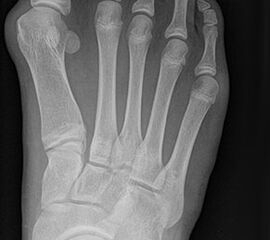

Bei einem juvenilen Hallux valgus handelt es sich um eine schon im Kindes – oder Adoleszentenalter 1 bestehende Valgusdeviation der großen Zehe bei Spreizfuß mit vergrößertem Intermetatarsalwinkel I / II aufgrund einer Adductionsstelllung des Metatarsale I – Metatarsaus primus varus.

Im Gegensatz zum Hallux valgus des Erwachsenen ist die Valgusabweichung der großen Zehe meist geringer ausgeprägt als bei Erwachsenen, der Intermetatarsalwinkel oft stark vergrößert. Die Angaben ab wann der Intermetatarsalwinkel als vergrößert gilt schwanken zwischen > 9° 2 und >14°3. Das Ausmaß der Beschwerden korrelieren nicht mit dem Auftreten und dem Schweregrad der Deformität (Zollinger 1990, Zollinger 1993). Begünstigend wirkt eine Schrägstellung des ersten Tarsometatasalgelenkes (Hefti 1998) und eine Hypermobilität dieses Gelenkes 2 in Kombination mit einer Bindegewebsschwäche. Häufig liegt eine positive Familienanamnese vor. In einer Untersuchung von Coughlin fand sich eine Vererbung über die mütterliche Linie in 72%, ein milder bis stark ausgeprägter Knick-Senkfuß in 17% (das entspricht der Quote von Knick-Senkfüßen in der Normalbevöl­kerung) aber in 22% ein Pes adductus, das ist wesentlich mehr als in der Normalbevölkerung zu erwarten wäre 4. Auch für Hefti (1998) gilt der Pes adductus als Komponente des Sichelfußes als begünstigend. Zur Inzidenz des Hallux valgus juvenilis finden sich je nach Autor verschiedene Angaben. Nach Auswertung von Schuluntersuchungen liegt die Häufigkeit zwischen 1,6 % bis 17% 56. Häufig tritt die Fehlstellung doppelseitig auf. Der Anteil der betroffenen Mädchen liegt 4-5x höher als bei Jungen (Lamprecht 2015).

Auch einige Syndrome gehen mit der Ausbildung eines ausgeprägten Spreißfuß mit Hallux valgus einher. Auf der Abbildung ein junger Erwachsener mit Trisomie 21.

• Pes metatarsus adductus